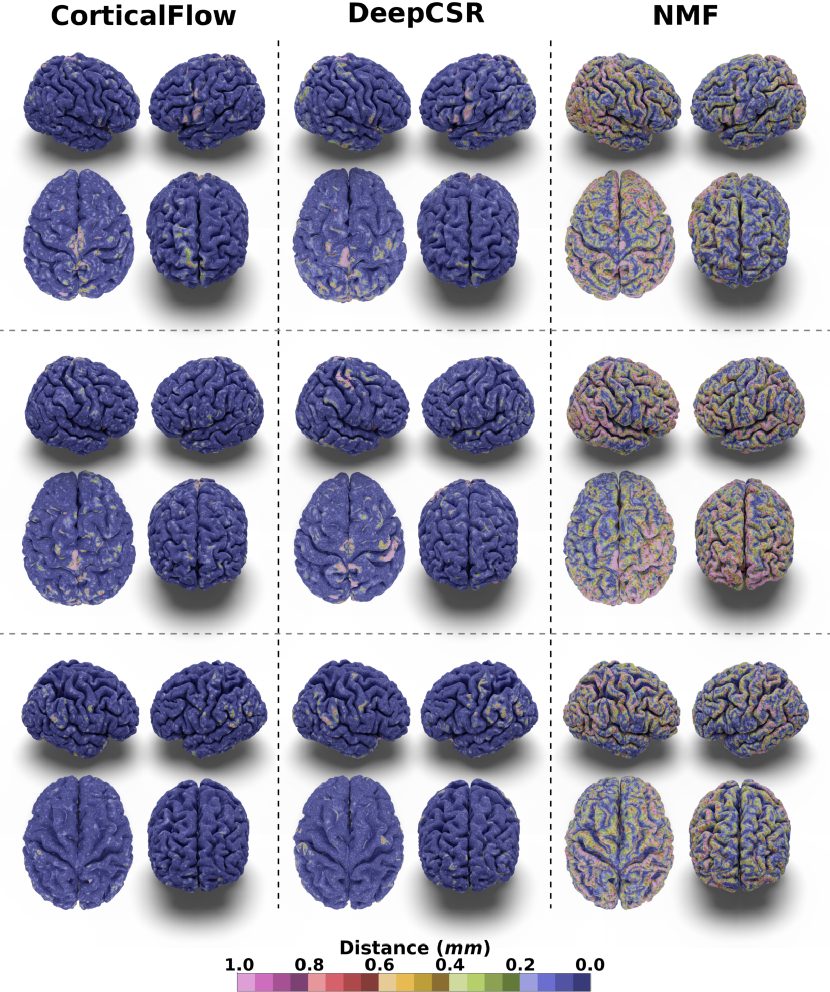

In our experiments, we noticed that CorticalFlow produces more geometrically accurate surfaces than the other methods. On average, it presents better geometric metrics across all the cortical surfaces. In addition, as shown in Figure 3, CorticalFlow errors are smaller () and evenly spread across the surface compared to the other methods. In contrast, NMF and DeepCSR can present substantial errors (). The former has its error spread across the entire surface, while the latter can produce large errors at specific regions.

CorticalFlow also generates triangular meshes with better properties than the evaluated methods. Compared to the deformation-based methods NMF and Voxel2Mesh, CorticalFlow predicted meshes are genus-zero surfaces and present a lower percentage of self-intersecting faces (mainly for the inner cortical surfaces). Figure 5(a) presents examples of self-intersecting faces produced by CorticalFlow, which are contrasted with the NMF predicted mesh for the same input MRI. The implicit-surface-based DeepCSR method does not produce a single self-intersecting face since it employs computationally expensive post-processing routines like topology correction [4] and iso-surface extraction. However, these post-processing routines do not take into account the input MRI which can generate non-plausible corrections on the output mesh as previously observed in Segonne et al. [67] and exemplified in Figure 5(b). Similarly, the voxel-wise segmentation baseline (i.e., QuickNAT) is free of self-intersecting faces, but it does not produce genus-zero surfaces. Indeed, QuickNAT’s predicted surfaces are composed of multiple connected components presenting many handles and holes which is not acceptable for the purpose of cortical surface reconstruction. Some examples of QuickNAT reconstructed cortical surfaces are presented in our supplementary material. Therefore, we argue that CorticalFlow is the method of choice to reconstruct regular surfaces from volumetric images.

Comparison with DeepCSR and NMF